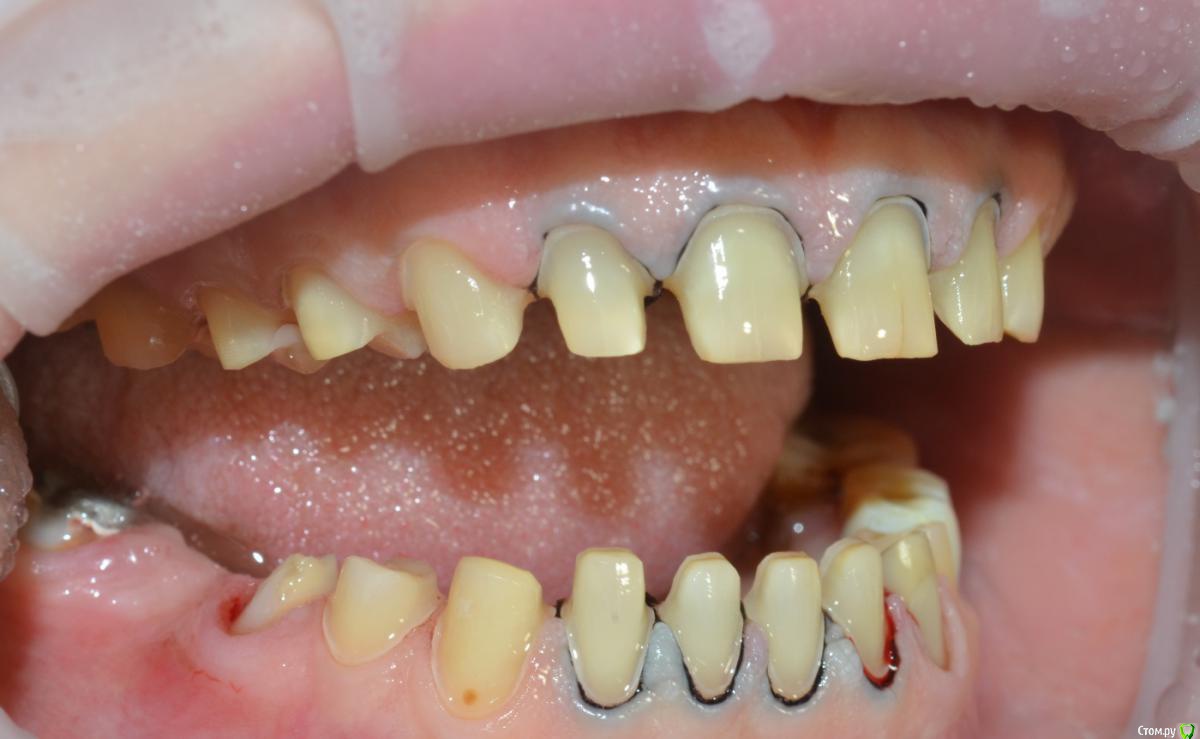

NazranDantist Опубликовано 21 мая, 2015 Поделиться Опубликовано 21 мая, 2015 (изменено) Коллеги поделитесь опытом. Какой план лечения предложить пациентке. Планируется тотальная работа что-нибудь из безметаловой технологии (E-max или претау, еще обдумываем). Вопрос, как выровнять оклюзионную плоскость, нужно ли прибегать к помощи ортодонта? Больше всего интересует первый сегмент, особенно зуб 15, висит слишком сильно. Или все таки стараться выйти из положения керамикой плюс хирургическое удлинение? Изменено 21 мая, 2015 пользователем NazranDantist Ссылка на комментарий

NazranDantist Опубликовано 4 сентября, 2015 Автор Поделиться Опубликовано 4 сентября, 2015 Продолжение кейса. Работа еще не закончена, зуб 25, 35, 36 - аббатменты на подходе, поэтому решили сделать после отпуска пациентки. Фото протокол не соблюдал, курс рубля прыгал, торопился в обменник . Вся работа - имакс на Цереке с редуцированием, фиксация - фронт на чойс, боковые - У-200. Ссылка на комментарий